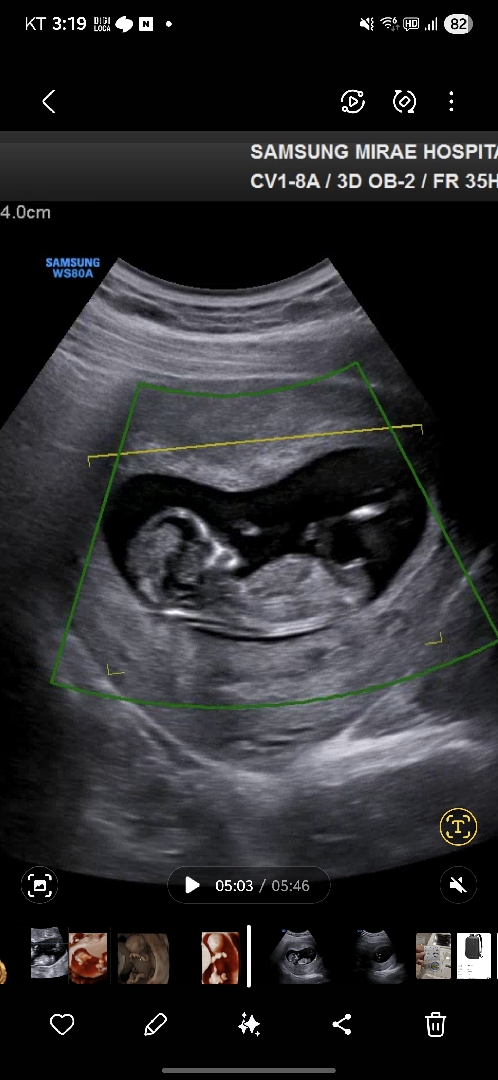

각도법 고수님들~12주 1일차에요! 헷갈려용 ㅠㅠ

12주 1일차 인데 이사진은 딸같아 보이는데 어떠셔요?! 댓글에 사진 하나 더 추가 할건데 그건 또 아들같아보이기도 하고 어렵네요 ㅠㅠ 도와주세요🥲

평행한게 딸같은 느낌이예요